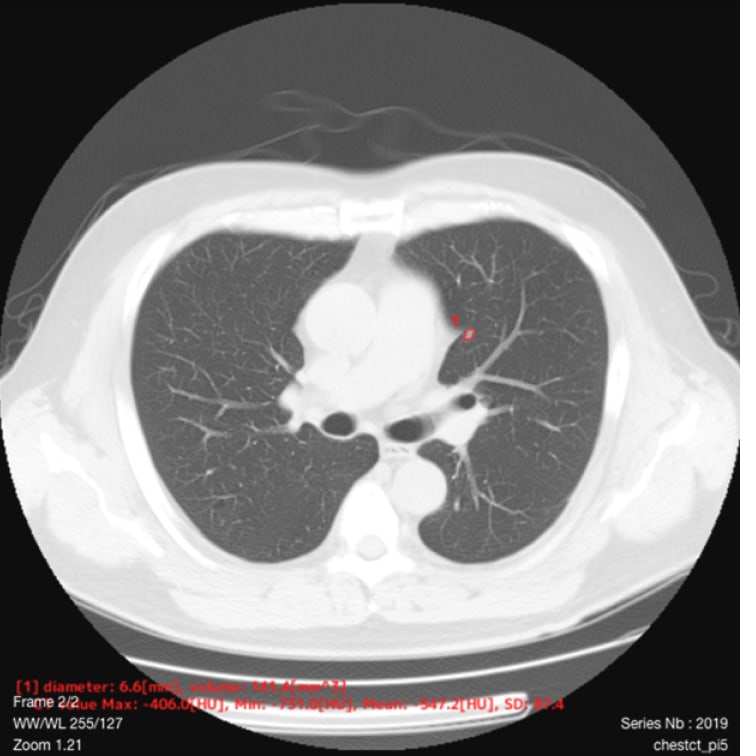

- 自動計測

- 検出した候補領域の大きさ:体積 [mm³] およびAxial断面最大径 [mm] を出力

- CT値:最大・最小・平均値・標準偏差を出力

標準線量CT